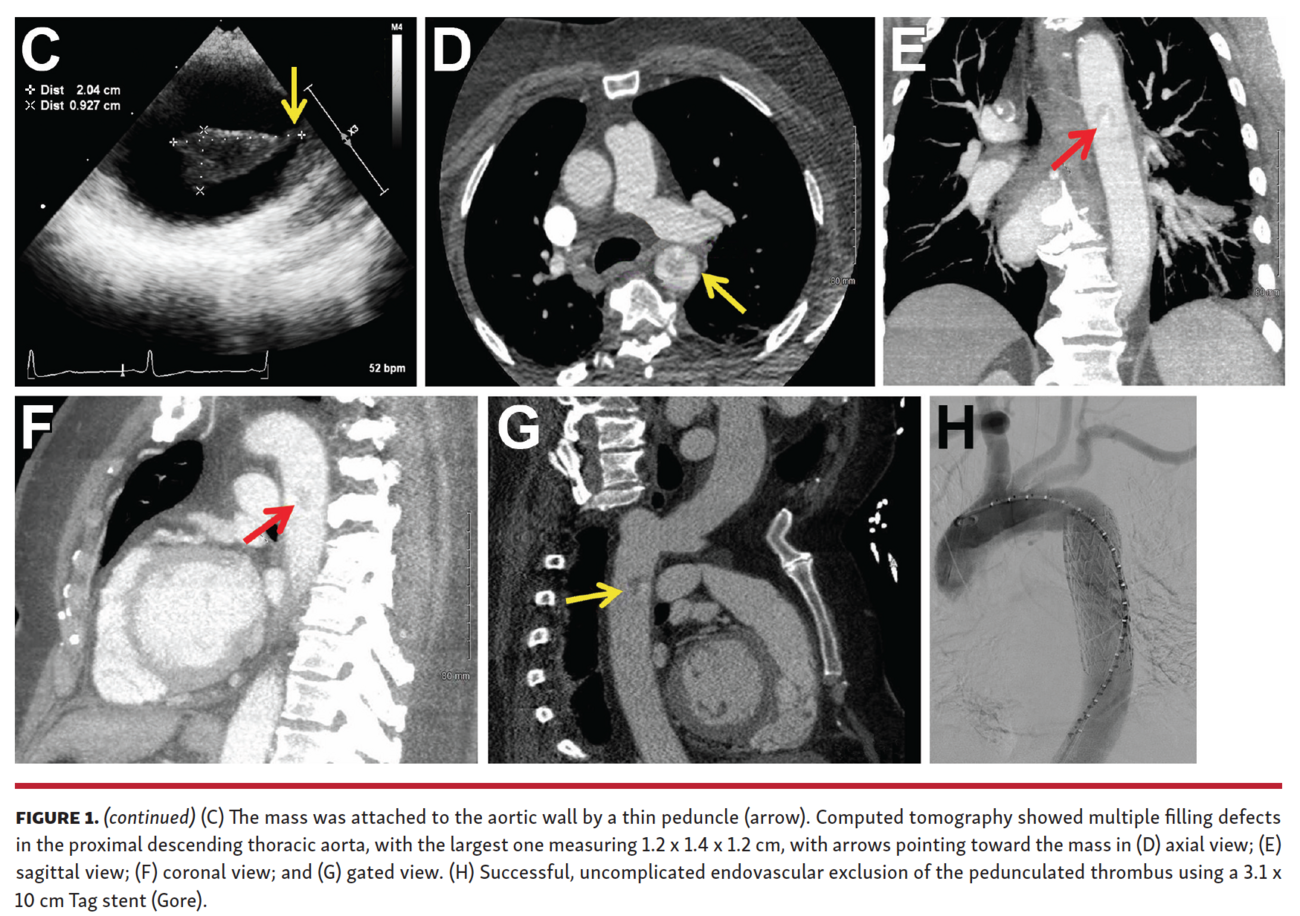

A 57-year-old woman was suspected of having embolic acute limb ischemia. An emergent angiogram showed flush occlusion of the right common femoral artery (Figure 1A). Surgical embolectomy was performed successfully, and pathology confirmed that the evacuated specimen was a blood coagulum. An exhaustive work-up for the embolic source was unrevealing until a transesophageal echocardiogram was obtained that showed a large, mobile mass (1.9 x 0.8 cm) in the descending thoracic aorta (Figure 1B; Videos 1 and 2) attached to the aortic wall by a thin peduncle (Figure 1C). Computed tomography showed multiple filling defects in the proximal descending thoracic aorta (Figures 1D-1G), with the largest measuring 1.2 x 1.4 x 1.2 cm. A complete hypercoagulable panel and age-appropriate cancer screening were both negative. The etiology of the mass was unclear; however, given the thromboembolic event, she underwent a successful, uncomplicated endovascular exclusion of the pedunculated thrombus using a 3.1 x 10 cm Tag stent (Gore) (Figure 1H). She was discharged on warfarin with a goal international normalized ratio of 2-3.